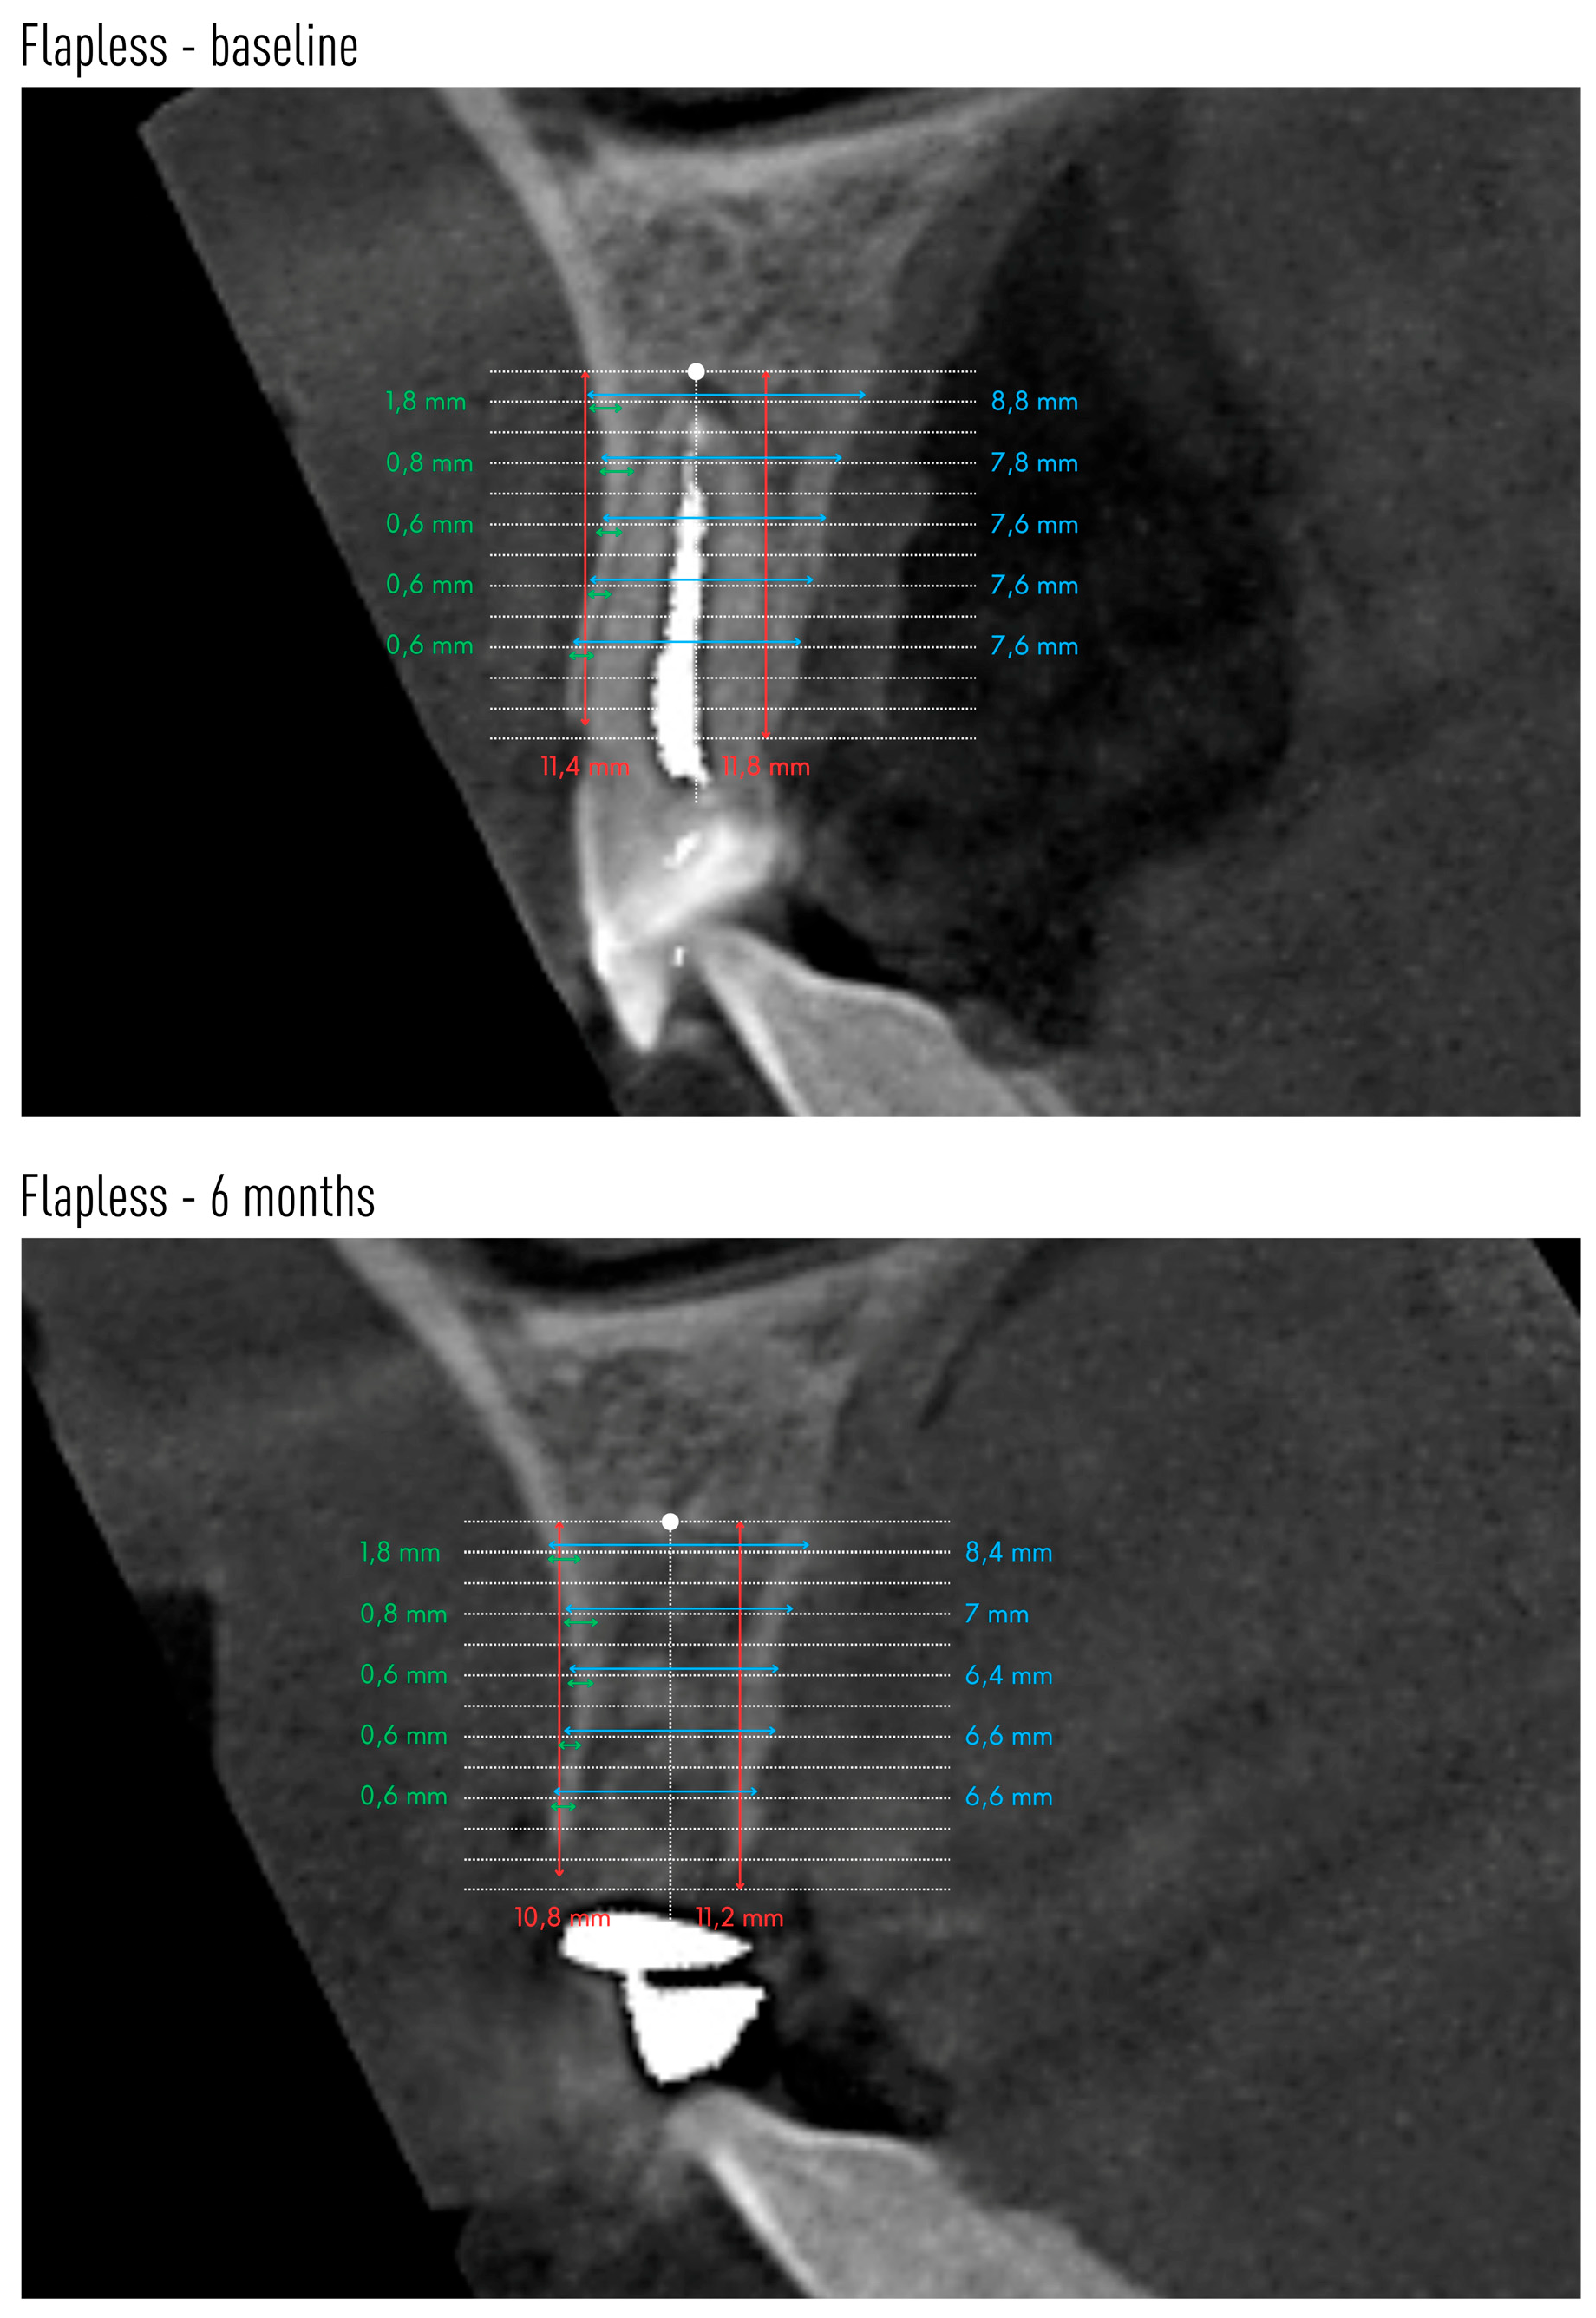

Cone-beam computed tomography (CBCT) was performed before tooth extraction and 6 months after the procedure. Sample scans with measurements marked are shown in Figure 5 (flapless group) and Figure 6 (flap group).

Figure 5.

An example CBCT scans of a patient allocated to flapless group with reference lines and measurements made on baseline and after 6 months.

Changes in the mean height of the buccal (BH) and lingual (LH) alveolar bone plates are shown in Table 5. The height of both plates decreased in both groups after 6 months. However, significant radiographic changes in BH and LH were observed only in the group without preparation of the mucoperiosteal flap. In group A, the buccal plate was reduced by an average of 1.08 mm, and the lingual plate by 1.29 mm. There were no statistical differences between the groups.

Changes in the anteroposterior alveolar buccal bone plate thickness (BBP) at 1 mm, 3 mm, 5 mm, 7 mm and 9 mm from the alveolar floor are shown in Table 6. The two groups did not differ with respect to these radiographic parameters before tooth extraction or 6 months after (except for BBP-9 before extraction). However, a decrease in the radiographic width of the vestibular lamina was observed, the greater the farther the measuring point was located from the alveolar floor. In the group with flap preparation, already at a height of 3 mm from the alveolar bottom, as well as 5 mm and 7 mm from the alveolar floor, the reduction in the width of the bone gained statistical significance. At a height of 9 mm from the alveolar floor, the average thickness of BBP9 was only 0.01 mm. In the flapless group, a significant decrease in the thickness of the vestibular compact plate was observed from BBP5 to BBP9.

Table 7 shows the changes in the mean alveolar horizontal width of the entire alveolar process. The radiographic width of the alveolar process was smaller 6 months after tooth extraction at each height in both groups. However, this reduction reached statistical significance only at heights of 5 mm and 7 mm in the flapless group.